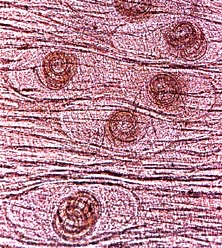

|

| Hình 1. Siêu câu trúc bề mặt Gnathostoma spinigerum (http://www. Stanford.edu) |